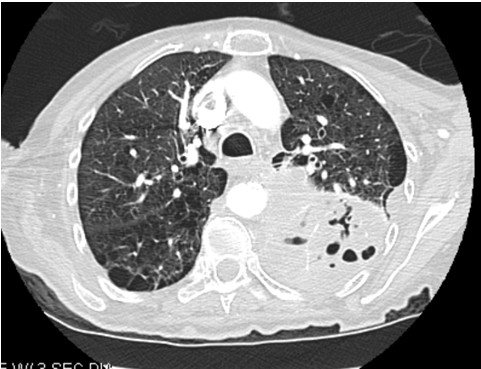

Within one month of discharge, patient returned to the emergency department with worsening cough, shortness of breath, hemoptysis and performance status. The patient received 65% of planned radiation treatments prior to arrival. Computed tomography scan of the chest revealed a 14x9x6 cm large mass like structure in the left lower lobe containing complex fluid and multiple pockets of air suggestive of an infected or necrotic tumor (Figure 3) (Figure 4) (Figure 5). Based on the progression and aggressiveness of the tumor, the patient decided to go on hospice. Shortly after, the patient died from respiratory failure.

Figure 3: Computed tomography scan of chest large mass like structure in the left lower lobe.

Figure 4: Computed tomography scan of chest showing large mass like structure in the left lower lobe containing complex fluid and multiple pockets of air suggestive of an infected or necrotic tumor.

Figure 5: Computed tomography scan of chest showing a 14x9x6 cm large mass like structure in the left lower lobe containing complex fluid and multiple pockets of air suggestive of an infected or necrotic tumor..